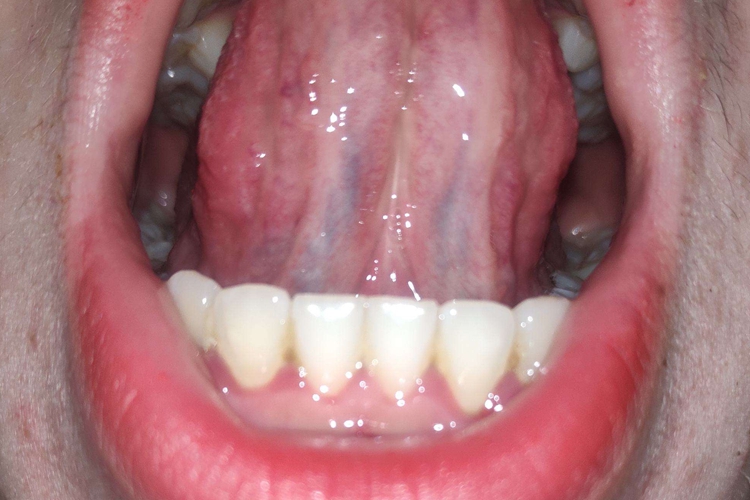

舌下的两根血管通常是指舌下静脉,上卷舌尖时可见两根静脉行于舌底,正常人仅隐隐显于舌下,其直径不超过2.7毫米,颜色也较浅,呈淡紫色。

舌下静脉异常可反应门静脉高压、血液循环功能障碍、二尖瓣疾病或肺气肿等疾病,仅可作为辅助判断。中医进行舌诊时也会观察舌下静脉,帮助辨证。此外,在心绞痛发作时用常采取舌下含服硝酸甘油,主要是因为舌下的黏膜较薄,且血运丰富,可使药物快速进行血液循环,进而发挥药效。